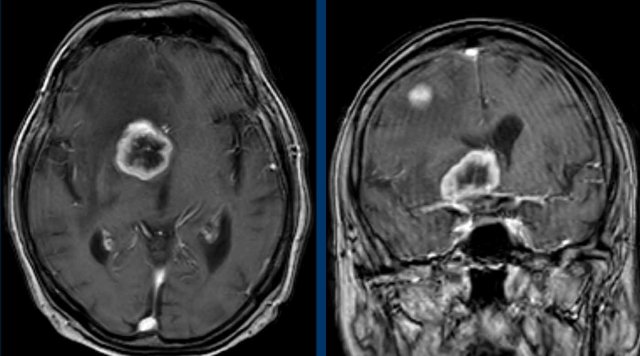

These images are of a 78-year old man who is known to have a squamous cell carcinoma of the floor of the mouth and complains of double vision.

At physical examination he is desorientated and has dysarthria and a Horner.

Based on these findings we assume that the Horner is caused by a central problem.

3D-T1 MPRAGE shows  a large ring enhancing lesion at the level of the hypothalamus on the right and a second lesion in the right hemisphere.

Conclusion

Metastases of a squamous cell carcinoma.

At other levels there were more metastases (circle).

The illustration shows the level of the pathology.